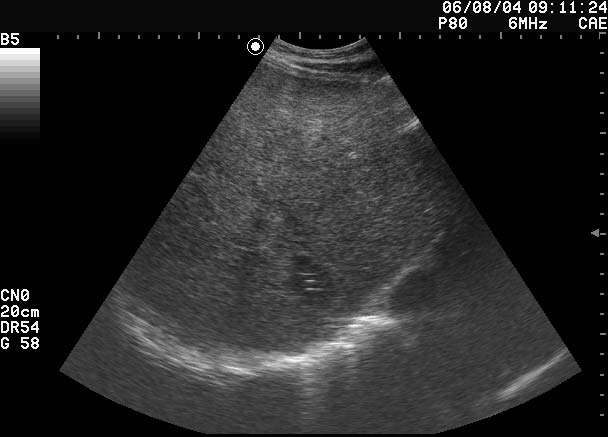

Все верно, абсцесс печени

Дренирован, динамика - см по числам в правом верхнем углу сонограмм